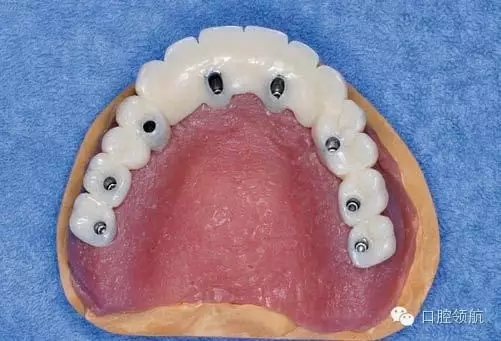

醫(yī)生在制作即刻負(fù)重的上部結(jié)構(gòu)時,應(yīng)把事先做好的臨時上部結(jié)構(gòu)(圖3)先分割開(圖4),再在口腔內(nèi)分幾次用快速聚合樹脂連接(圖5)。

圖3 事先做好的臨時上部結(jié)構(gòu)。

圖4 先把做好的臨時上部結(jié)構(gòu)全部分割開。